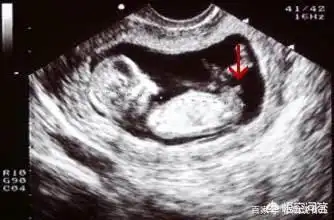

怀孕十二周可以从b超中的小肿块分辨男女,这真的可以看出来吗?